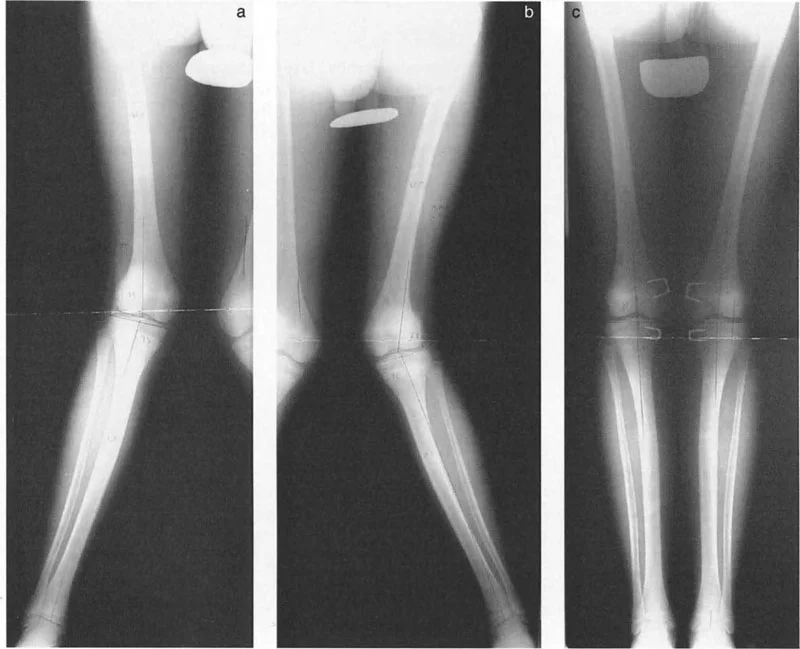

القياسات الشعاعية الدقيقة

تعتبر الأشعة السينية (Orthoroentgenograms) هي الأداة الأساسية لقياس أطوال العظام بدقة. يتم أخذ صور شعاعية للطرفين السفليين معًا لتقييم طول الفخذ والساق بشكل فردي. هذه القياسات ضرورية لتحديد مقدار التفاوت الحالي.

متى يتم إجراء تثبيت الصفيحة المشاشية

يعتبر التوقيت هو المفتاح لنجاح عملية تثبيت الصفيحة المشاشية. تستخدم طريقة المضاعف لحساب العمر الأمثل لإجراء العملية لضمان تحقيق التصحيح المطلوب بحلول وقت النضج الهيكلي دون تصحيح مفرط.

- الصيغة: المضاعف عند عمر تثبيت الصفيحة المشاشية (ME) = (L × M) / (L × M - E/K)

- بعد حساب ME، يتم الرجوع إلى جدول المضاعفات لتحديد العمر الزمني المقابل.